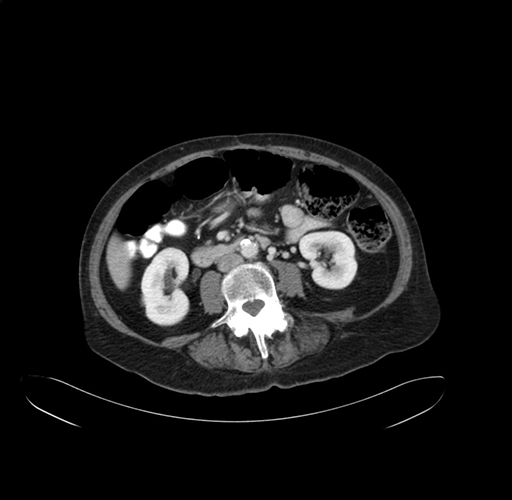

Pre-Chemo: Axial Venous

Axial Venous